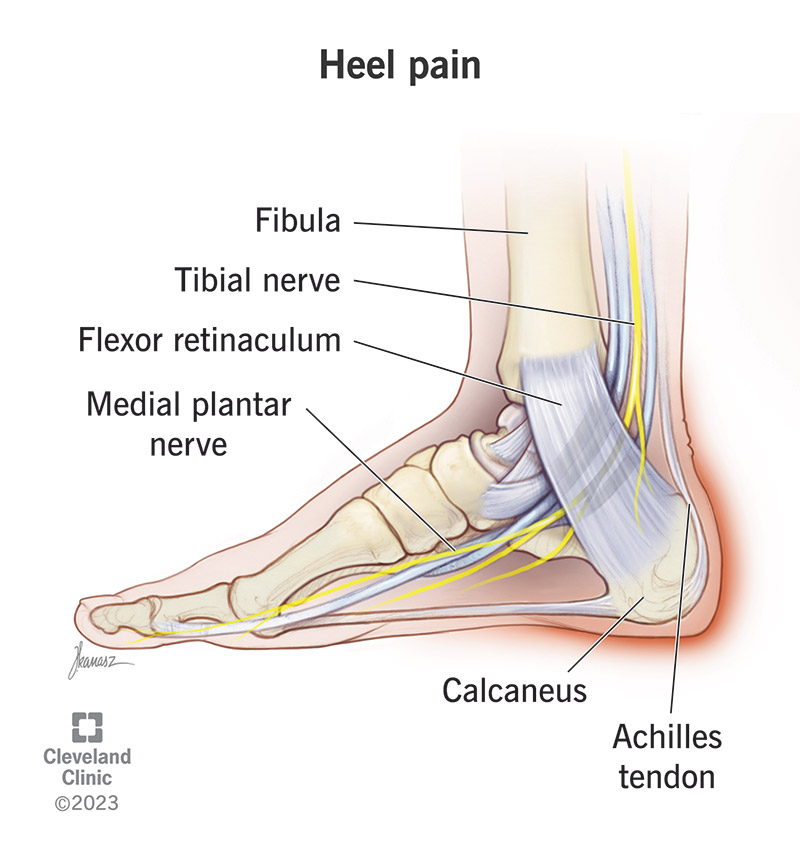

Heel Pain Causes and Treatment

Common Conditions Causing Heel Pain

Heel Pain Causes Diagnosis Treatment